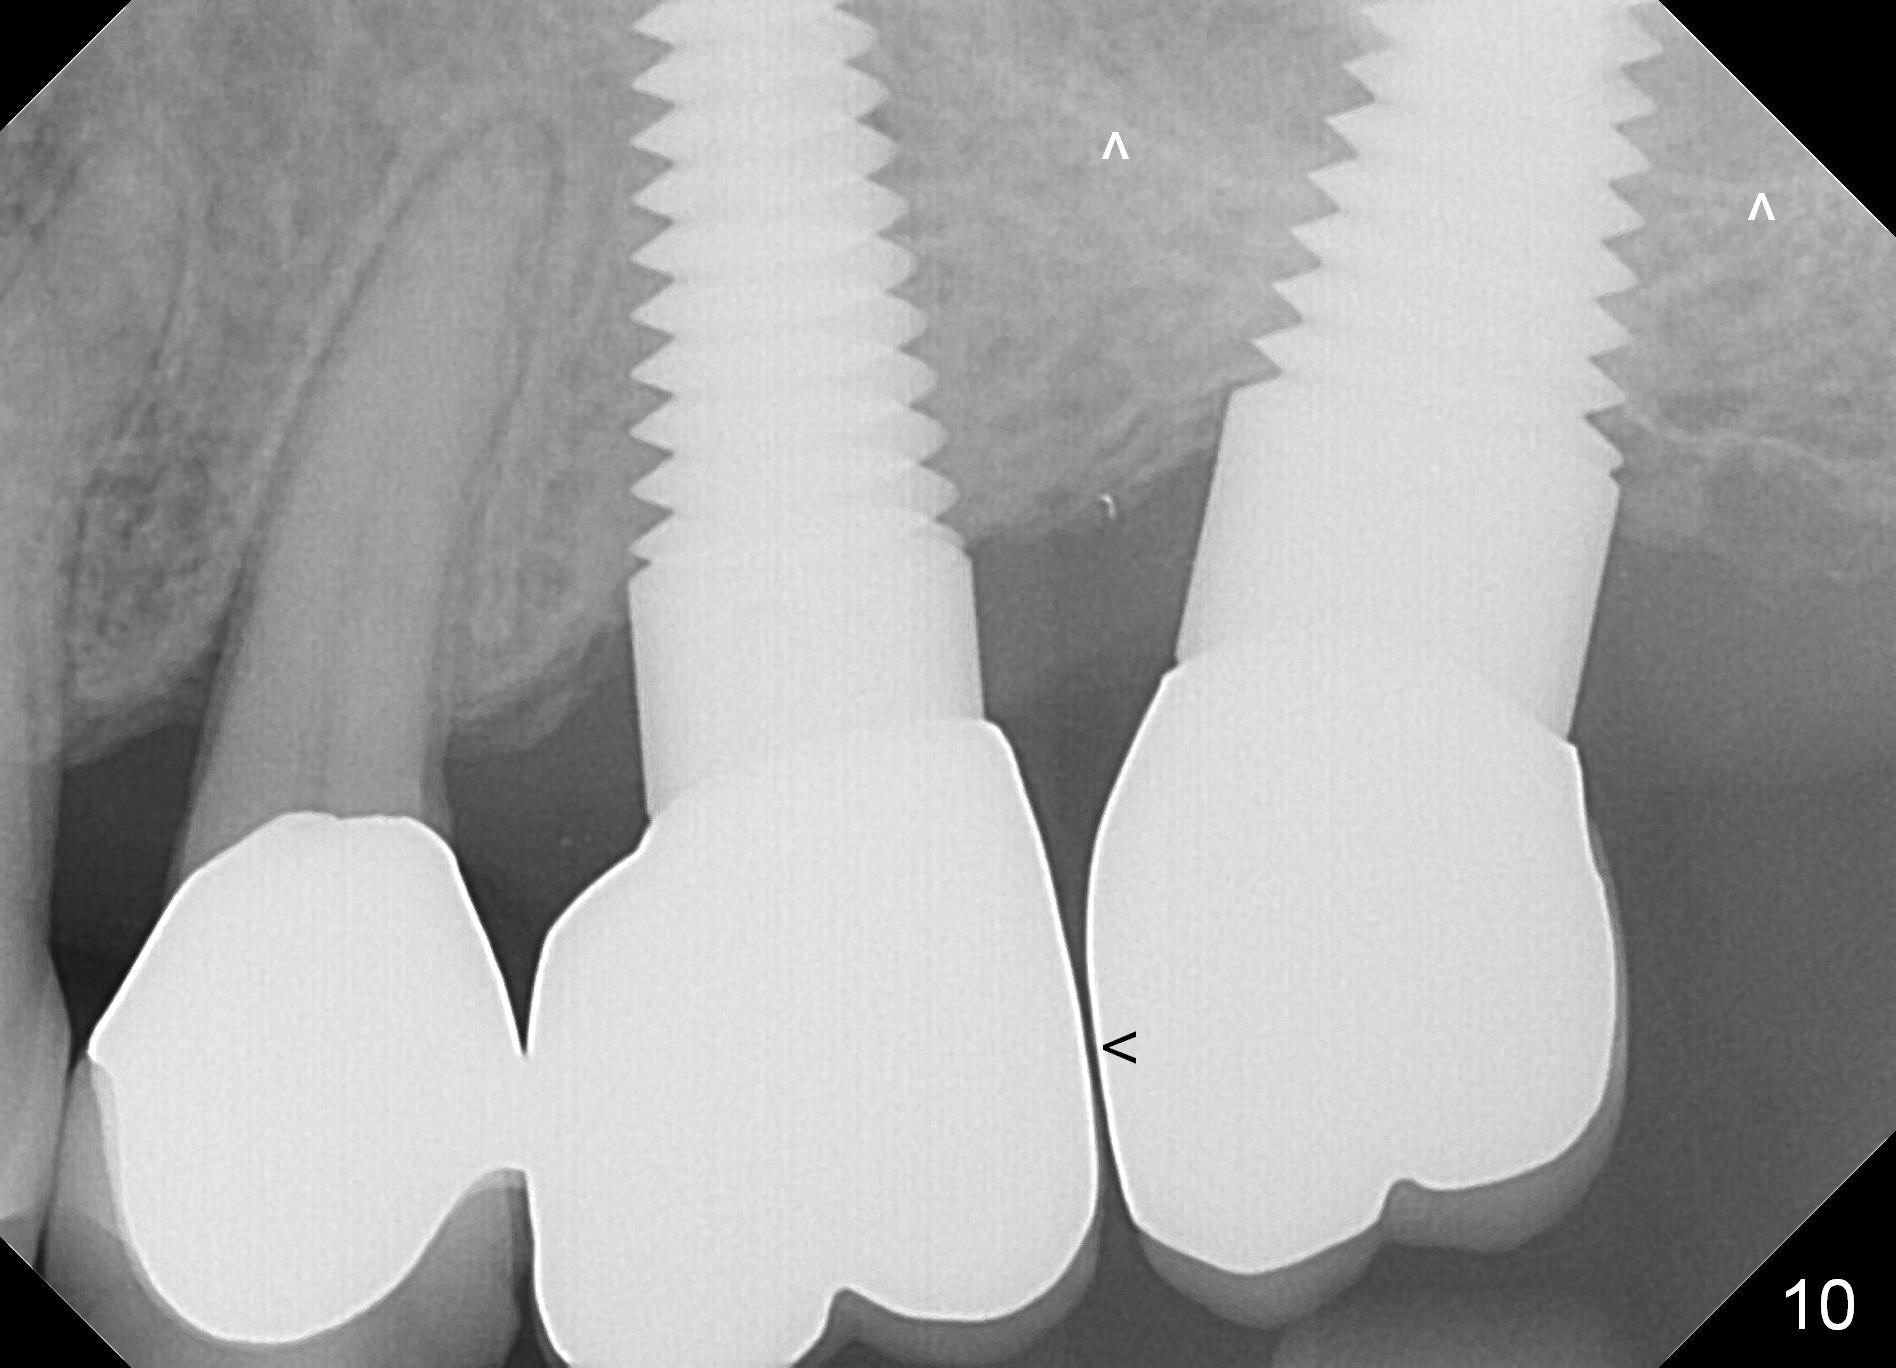

A 58-year-old man used to have a upper left 3-unit bridge. Two months after extraction and immediate implant at the site of the posterior abutment, an implant is planned to be placed at the site of the pontic, #14 (Fig.1). Osteotomy starts with a 1.6 mm pilot drill, followed by bone expanders, parallel to the crown of the tooth #13. The first intraop PA shows that 3.0 mm bone expander is close to the root of the neighboring tooth (Fig.2). No matter what is done to change the trajectory of the osteotomy using expanders according to the crown morphology of the neighboring tooth, the next 3 expander does not improve in parallelism (Fig.3). When a 6x17 mm tap is inserted (Fig.4 T), it is realized that axis of the tap is parallel to the axis of the crown of the neighboring tooth (black line), but not that of the root (red line). It is too late to change the trajectory drastically; a 6x17 mm implant is placed with insertion torque > 60 Ncm (Fig.5). It is best to change the trajectory as early as possible, e.g., after taking the first intraop PA and withdrawing the expander (Fig.6 black area) and as much as possible (red line; starting new osteotomy). It is quite similar to immediate implant. There is no bone loss 2 months postop (Fig.7), 18 months (Fig.8,9) or 34 months (Fig.10)post cementation, in spite of open contact between the crowns (Fig.10 black arrowhead). This is partially due to supragingival margin (Fig.11,12 (immediately pre-cementation)). No bone loss is noted 3 years 5 months post cementation (Fig.13).